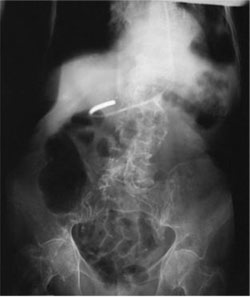

The abdomen image below could be improved by:

1. Aligning the

midsagittal plane to the center of the IR

2. Collimating to skin

surface

3. Decreasing mAs

- 2 only

- 3 only

- 1 and 2 only

- 1, 2, and 3

1, 2, and 3